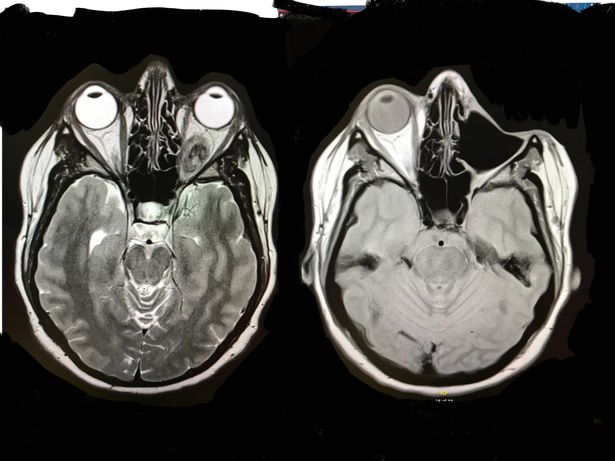

An MRI scan found a huge tumor growing behind her eye and a biopsy in April 2018 was taken to see if it could still be saved.